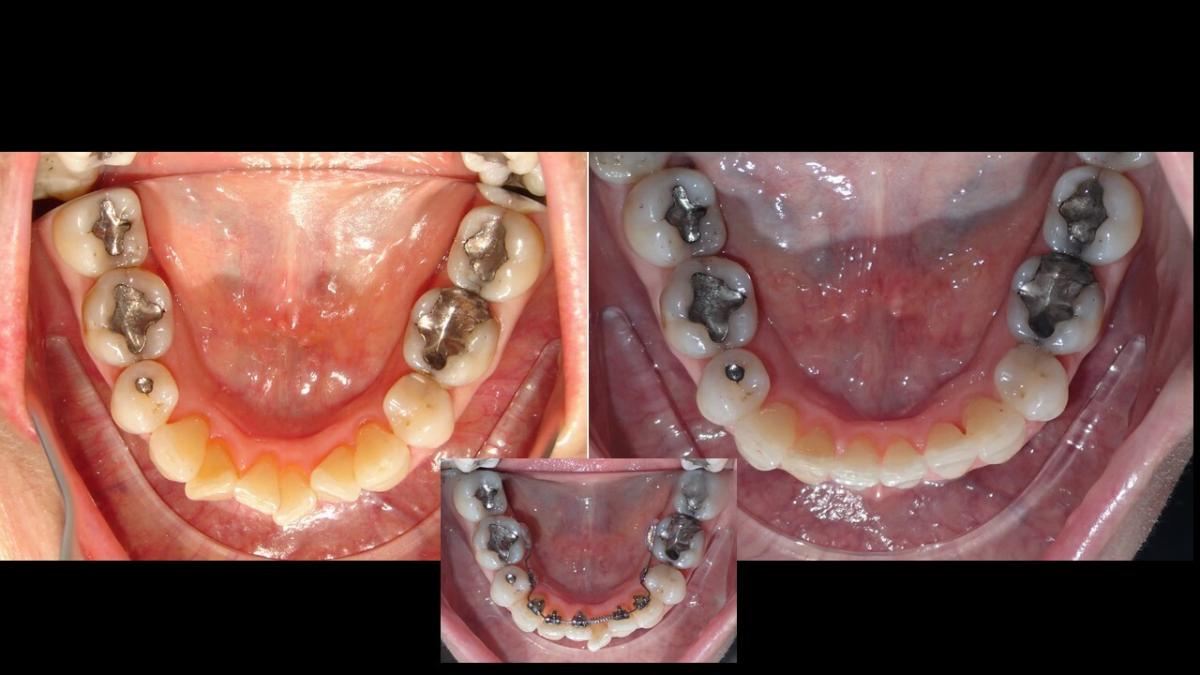

Galería de Sonrisas

large-Ortodoncia Lingual

large-Ortodoncia lingual invisible

large-Lingual